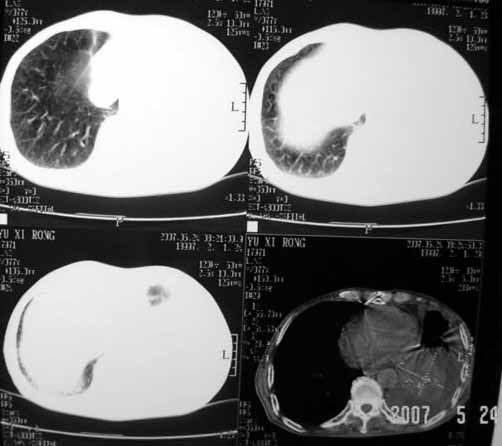

以下是引用luochengyi在2007-5-24 14:33:00的发言:[br]考虑左下肺癌。左侧胸腔积液。

以下是引用adams在2007-5-24 17:12:00的发言:[br]支持“考虑左下肺癌,左侧胸腔积液,建议胸水检查”。[br] [br]

以下是引用fumaogui在2007-5-24 16:20:00的发言:[br]左侧胸腔积液.[br]左下叶不张考虑中心型肺癌[br]建议纤支镜检查.